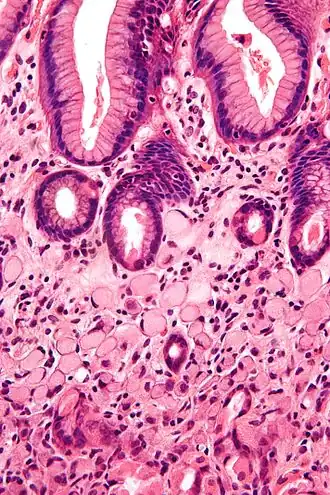

Zegelringcel, zoals te zien bij een colonadenocarcinoom met een vacuole van mucine. -

De naam van de cel komt door zijn uiterlijk; zegelringcellen lijken op een zegelring. Ze bevatten een grote hoeveelheid mucine, die de celkern naar de celperiferie duwt. De plas mucine in een zegelringcel bootst het uiterlijk na van een gat waar een vinger doorheen kan en de kern bootst het uiterlijk van de voorkant van de ring in profiel na.